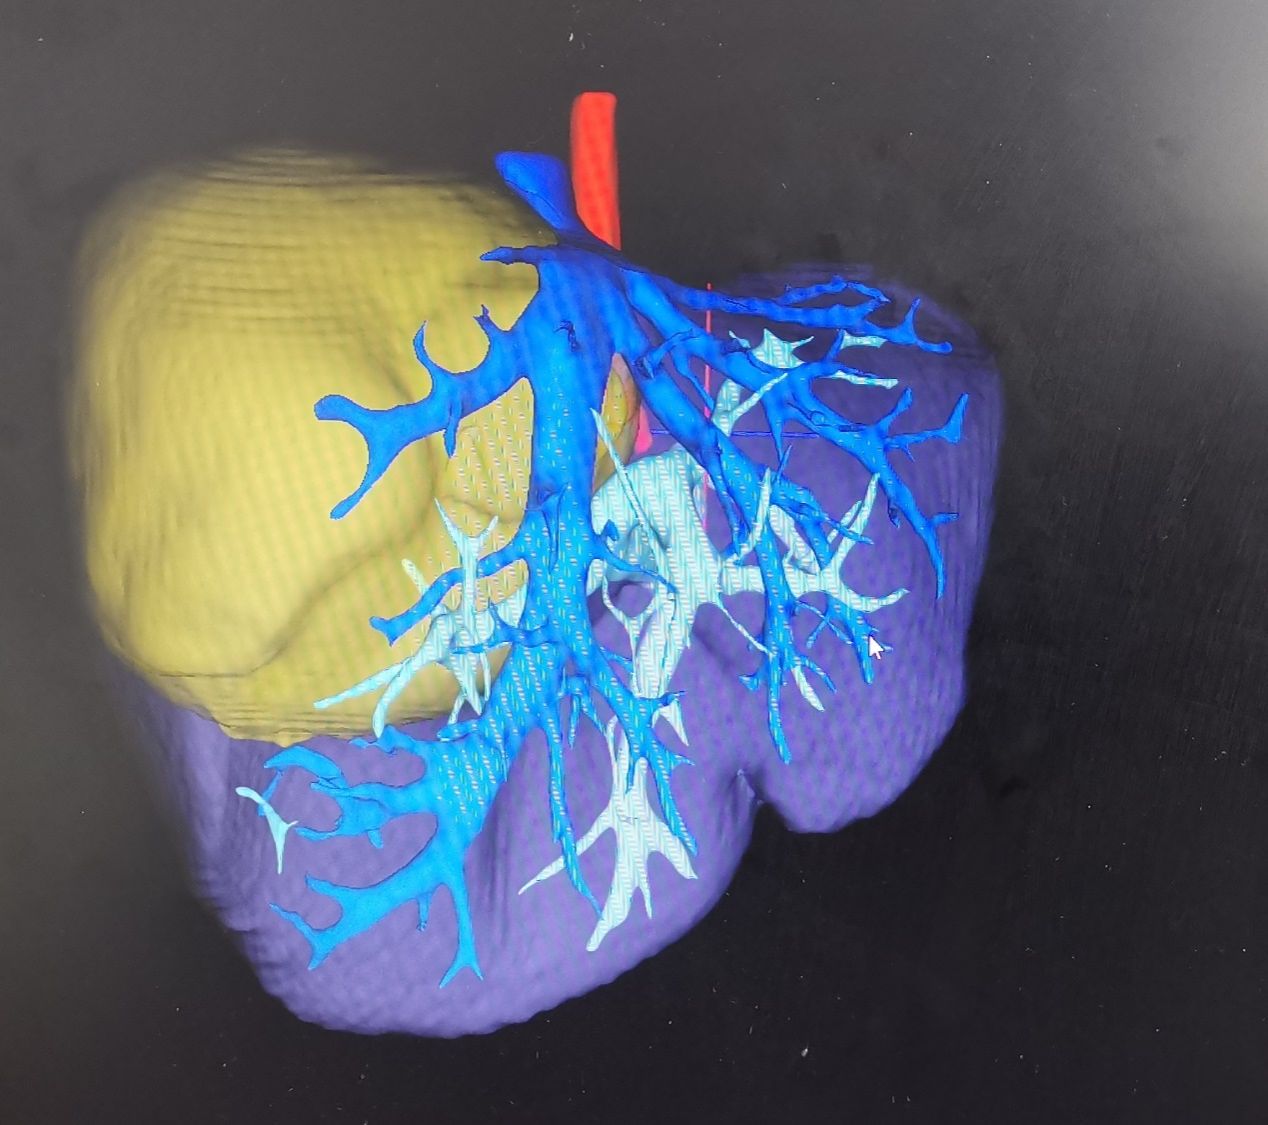

据李鹏教授介绍,该患儿2年前曾于宁夏某医院手术治疗后恢复良好。3月初复查时发现肝脏肿瘤,慕名来到我院,进一步完善各项检查,根据患儿病情和病理结果最终确诊肾上腺皮质癌伴肝转移,目前患儿一般情况良好,没有表现不适症状。该病在儿童中发病率仅为0.2~0.3/百万,属极罕见恶性肿瘤。影像显示,腹膜后肿瘤最大径约15cm,肝右叶存在转移并累及右半肝脏的血管、胆道,更为棘手的是肿瘤紧密包绕肝后段下腔静脉,导致影像学上的下腔静脉结构模糊。此类病例手术风险极高:既要尽可能彻底切除肿瘤,又需保护重要血管功能,稍有不慎可能导致大出血或器官损伤,对外科团队的技术与应变能力提出极致挑战。

为确保治疗方案科学合理有效安全,小儿外科组织邀请肝胆胰与肝移植外科、泌尿外科、影像介入科、儿科、肿瘤内科、麻醉科、病理科、血管外科等相关科室进行全院专家多学科会诊(MDT)。专家一致认为,手术是目前最有效的治疗方法,但需要面临肝后下腔静脉受累导致肿瘤侵犯下腔静脉无法完全切除肿瘤,需要切除下腔静脉进行人工血管替代,或姑息性切除而残余肿瘤。但是使用人工血管容易导致血栓形成而长期服用抗凝药物,小孩处于青春期快速生长血管代偿等问题。经讨论综合评估,手术前介入科协助行肿瘤供血动脉栓塞,以减少手术中出血,李鹏教授与曲凯教授团队联合,尽最大努力根据术中情况将肿瘤自下腔静脉剥离;术前准备人造血管随时备用,以防万一;为患儿生命加上“双保险”。

5小时鏖战:精准“拆弹”零误差